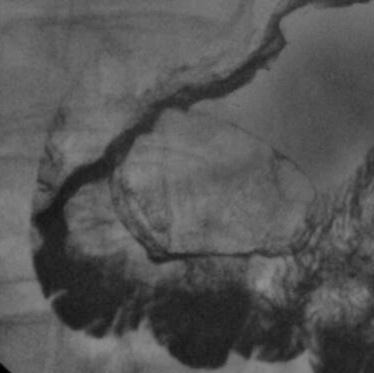

Значит то огромное депо бария , что был виден по нисходящей ДПК до атропинизации-дивертикул? нижняя стенка антрального отдела после атропинизации ригидна, с неровными, зазубренными контурами, в условиях двойного контрастирования также дефект наполнения с депо бария в нем. Логично предпложить после ваших  подсказок рак головки с прорастанием нижней стенки желудка и с изъязвлением.

Контур антрального отдела желудка по большой кривизне зазубрен (возможно, именно возможно, а не утверждение - зазубрены являются изъязвлениями слизистой оболочки) - красные стрелки.

По большой кривизне антрального отдела визуализируется (намечается) полицикличность контура.- бирюзовые стрелки.

Увеличение "дуоденального окна" (разворота 12-ти перстной кишки) - зелёный круг и обнажение флексура дуоденоеюналис - сиреневые стрелки свидетельствуют об увеличении поджелудочной железы, в частности головки.

Все вышеупомянутое позволяет высказать предположение, что "первичный процесс" локализуется в поджелудочной железе, а "поражение желудка" - вторично.

Операция проходила в областном онкологическом центре, где работает коллега Рыбакова, со слов её знаю, что было злокачественное новобразование поджелудочной железы, с инфильтрацией стенки желудка.

Спасибо, а по локализации в поджелудочной железе более точных данных нет: в хвосте? в теле?в головке? Могу предположить, что не в головке, т.к. рельф слизистой подковы 12-перстной кишки, практически не изменён.

Головка и тело.